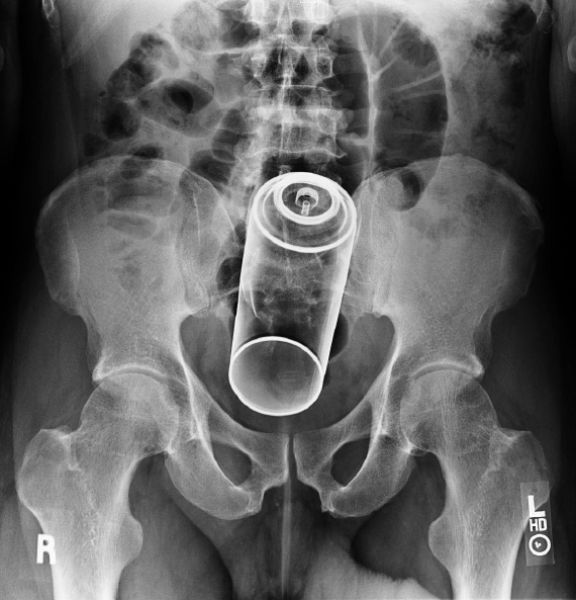

Impulse Body Spray